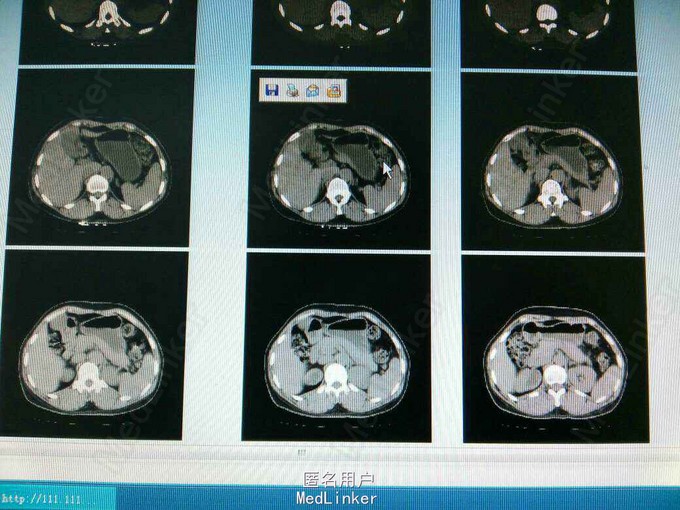

ct提示右侧双肾输尿管畸形,输尿管囊肿。总肾功能正常,尿常规正常,未发现结石等异常,右上位肾脏及输尿管扩张。